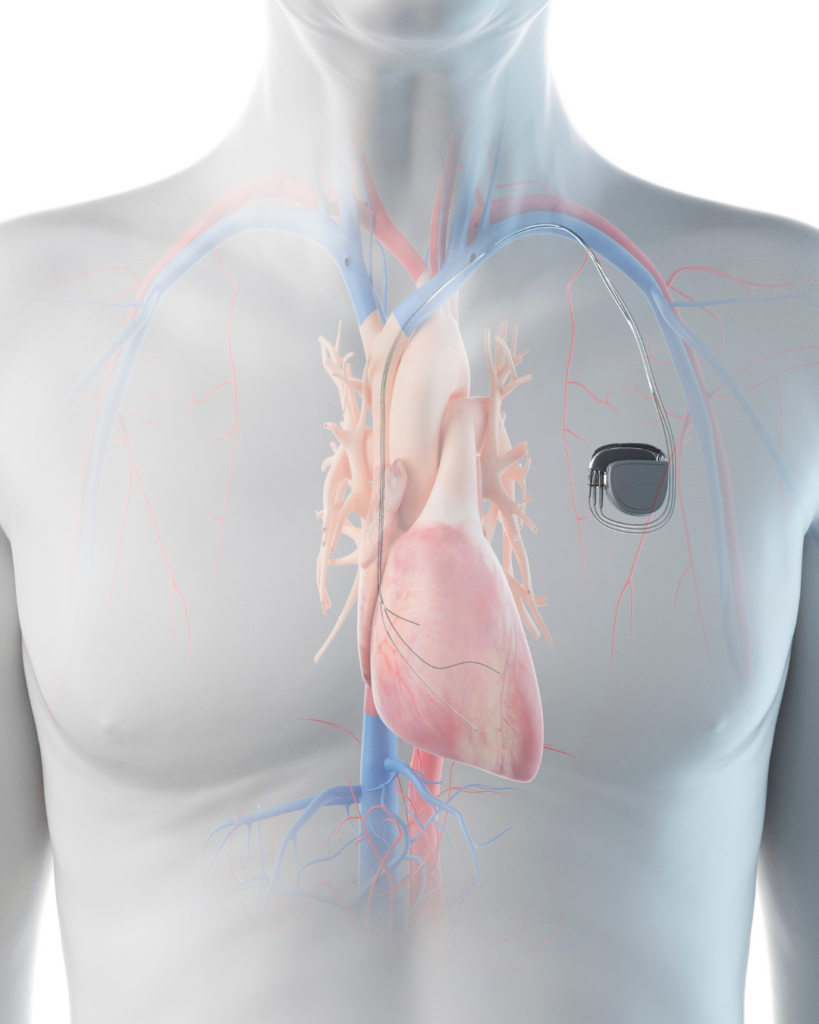

Ο βηματοδότης είναι μια ηλεκτρονική συσκευή που εμφυτεύεται κάτω από το δέρμα, συνήθως στην περιοχή κάτω από την κλείδα, και έχει ως βασική λειτουργία τη ρύθμιση του καρδιακού ρυθμού. Η συσκευή αποτελείται από μία γεννήτρια παλμών και ένα ή δύο ηλεκτρόδια που τοποθετούνται μέσα στις κοιλότητες της καρδιάς. Ο ρόλος του βηματοδότη είναι να στέλνει ηλεκτρικά σήματα στην καρδιά όταν ανιχνεύει ότι ο φυσιολογικός ρυθμός έχει διαταραχθεί ή επιβραδυνθεί επικίνδυνα.

Κατά τη διάρκεια της επέμβασης, ο καρδιολόγος εισάγει το ηλεκτρόδιο μέσω φλέβας και το τοποθετεί στις κατάλληλες κοιλότητες της καρδιάς. Στη συνέχεια, η γεννήτρια παλμών συνδέεται με τα ηλεκτρόδια και τοποθετείται κάτω από το δέρμα. Η λειτουργία της συσκευής δοκιμάζεται και προγραμματίζεται ανάλογα με τις ανάγκες του ασθενούς.